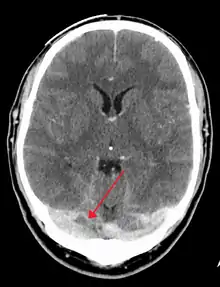

There are various neuroimaging investigations that may detect cerebral sinus thrombosis. Cerebral edema and venous infarction may be apparent on any modality, but for the detection of the thrombus itself, the most commonly used tests are computed tomography (CT) and magnetic resonance imaging (MRI), both using various types of radiocontrast to perform a venogram and visualise the veins around the brain.[2]

Computed tomography, with radiocontrast in the venous phase (CT venography or CTV), has a detection rate that in some regards exceeds that of MRI. The test involves injection into a vein (usually in the arm) of a radioopaque substance, and time is allowed for the bloodstream to carry it to the cerebral veins - at which point the scan is performed. It has a sensitivity of 75-100% (it detects 75-100% of all clots present), and a specificity of 81-100% (it would be incorrectly positive in 0-19%). In the first two weeks, the "empty delta sign" may be observed (in later stages, this sign may disappear).[6]